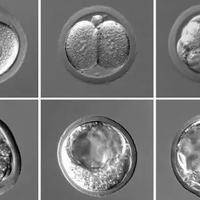

在试管过程中,有一种技术叫养囊,通过将受精卵培养至5天后发育成囊胚,再将囊胚移植到母体子宫内,增加受孕率和优生率。该技术适用于多种不孕症,如输卵管堵塞、子宫内膜异位症等。试管养囊技术具有较高的成功率,同时也能减少多胎妊娠的风险。在使用试管养囊技术前,医生需要根据患者的身体状况和病史进行综合评估,制定适合的治疗方案。